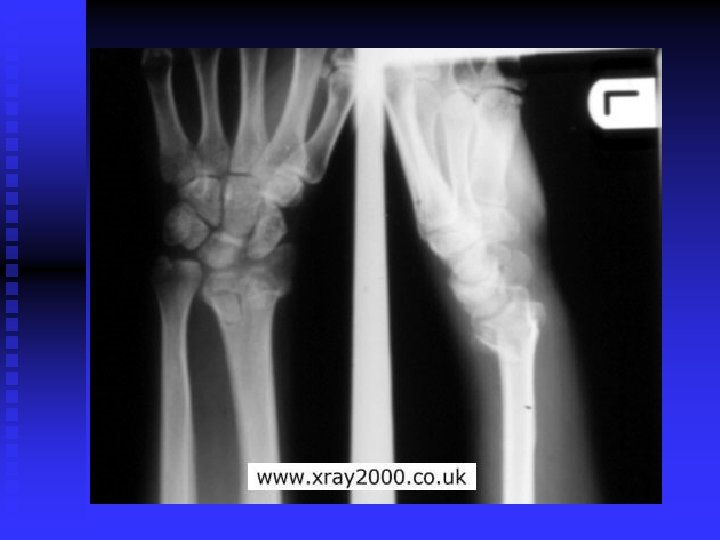

Colles’ Fracture MOI: Fall on outstretched hand n S&S: Forward displacement of the radius, others are same as forearm fracture n TX: RICE, and casting n